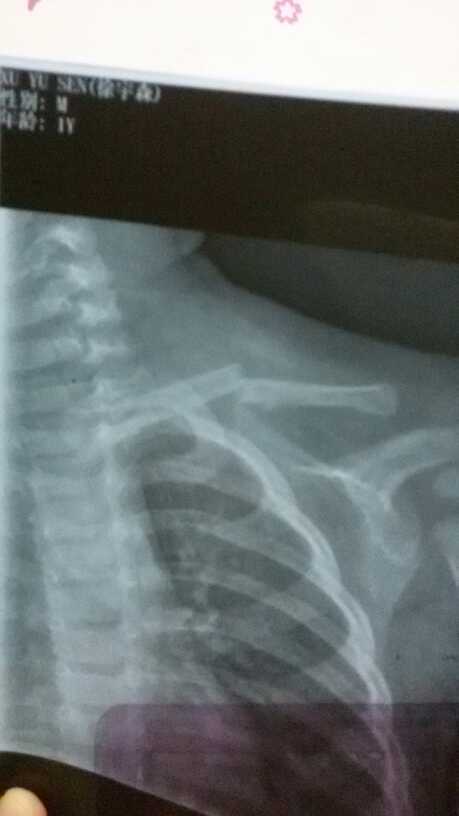

是骨科医生的帮帮我,帮我看看,我应该怎么做,锁骨骨折了,才一岁的孩子谁忍心让他做手术啊 点击展开 母婴用户147216882 2015-10-01 12:01 满意回答 您这情况建议手术治疗,因为小孩逼沃揭一岁保守治疗的话可能录渐小孩配合不好,手术其实损伤小,愈合快,报菠不然的话可能会畸形愈合。希望可以帮到您祝早日康复 ױ 2015-10-01 12:06 宝宝知道提示您:回答为网友贡献,仅供参考。 相关问题 宝宝出生10天了,才发现肩膀那里摸上去硬硬的,后来带到医院拍片,结果锁骨骨折,后来骨科医生说没事的 急!!!7岁小孩在学校发生意外事故,致右锁骨骨折,该谁负责! 你好!我儿子三岁多在幼儿园玩滑梯的时候摔下来了 去检查结果说是左锁骨骨折!现在想让学校赔偿!请问到